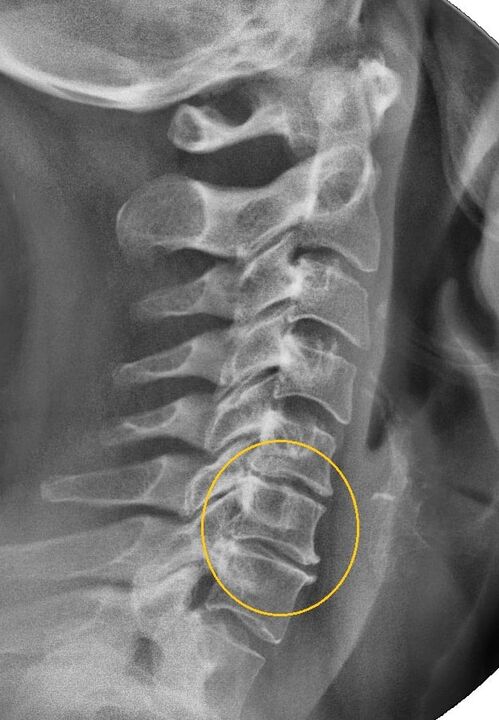

Das aussagekräftigste diagnostische Verfahren ist die Radiographie. Pathologien 1. Grades entsprechen dem 1. oder 2. radiologischen Stadium. Die resultierenden Bilder visualisieren typische Krankheitszeichen.

| Röntgenstadien der zervikalen Osteochondrose 1. Grades | Charakteristische Zeichen |

|---|---|

| Stufe 1 | Kleinere Veränderungen der Krümmung der Wirbelsäule im Halsbereich, die ein oder mehrere Segmente betreffen |

| Stufe 2 | Leichte Verdickung der Bandscheiben, Verformung der Processus uncinatus, Aufrichtung der Lordose, geringfügige Wucherungen der Knochenstrukturen |